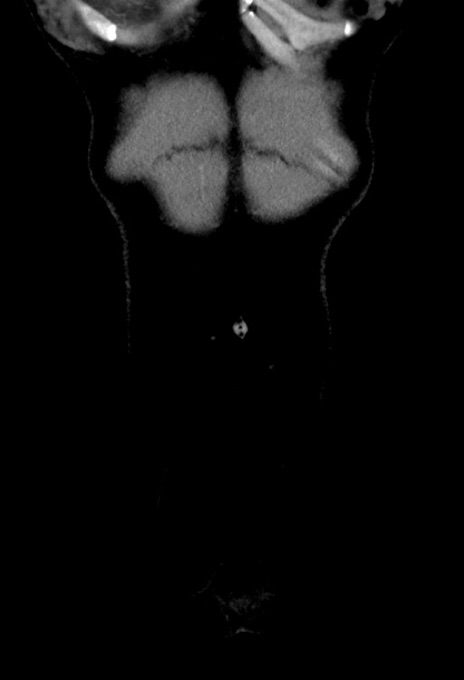

症例17(冠状断像)

【症例】20歳代女性

【主訴】嘔吐、下腹部痛

【現病歴】昨日夕食後に嘔吐し下腹部痛が出現。本日になっても嘔吐持続し改善しないため来院。

【身体所見】意識清明、BT 37.2℃、BP 108/67mmHg、腹部:平坦、やや硬、下腹部正中から右にかけて圧痛あり、反跳痛軽度あり、tapping pain(+)。

【データ】WBC 13600、CRP 14.94